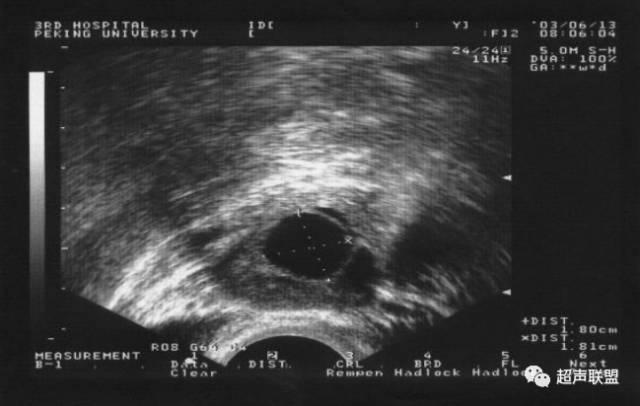

自然周期待體溫上升後,超聲波監測卵泡是否消失或塌陷,預示已經排卵。促排卵周期或人工授精周期,在卵泡直徑>18~20mm時,預示卵泡已經成熟,可以注射HCG,48小時後觀察卵泡是否已經排掉。

當優勢排卵發育成熟至直徑18~23mm,自然周期可以自測基礎體溫,升高>0.2℃(大約36.7°以上)後複查超聲波,觀察是否已經發生排卵。